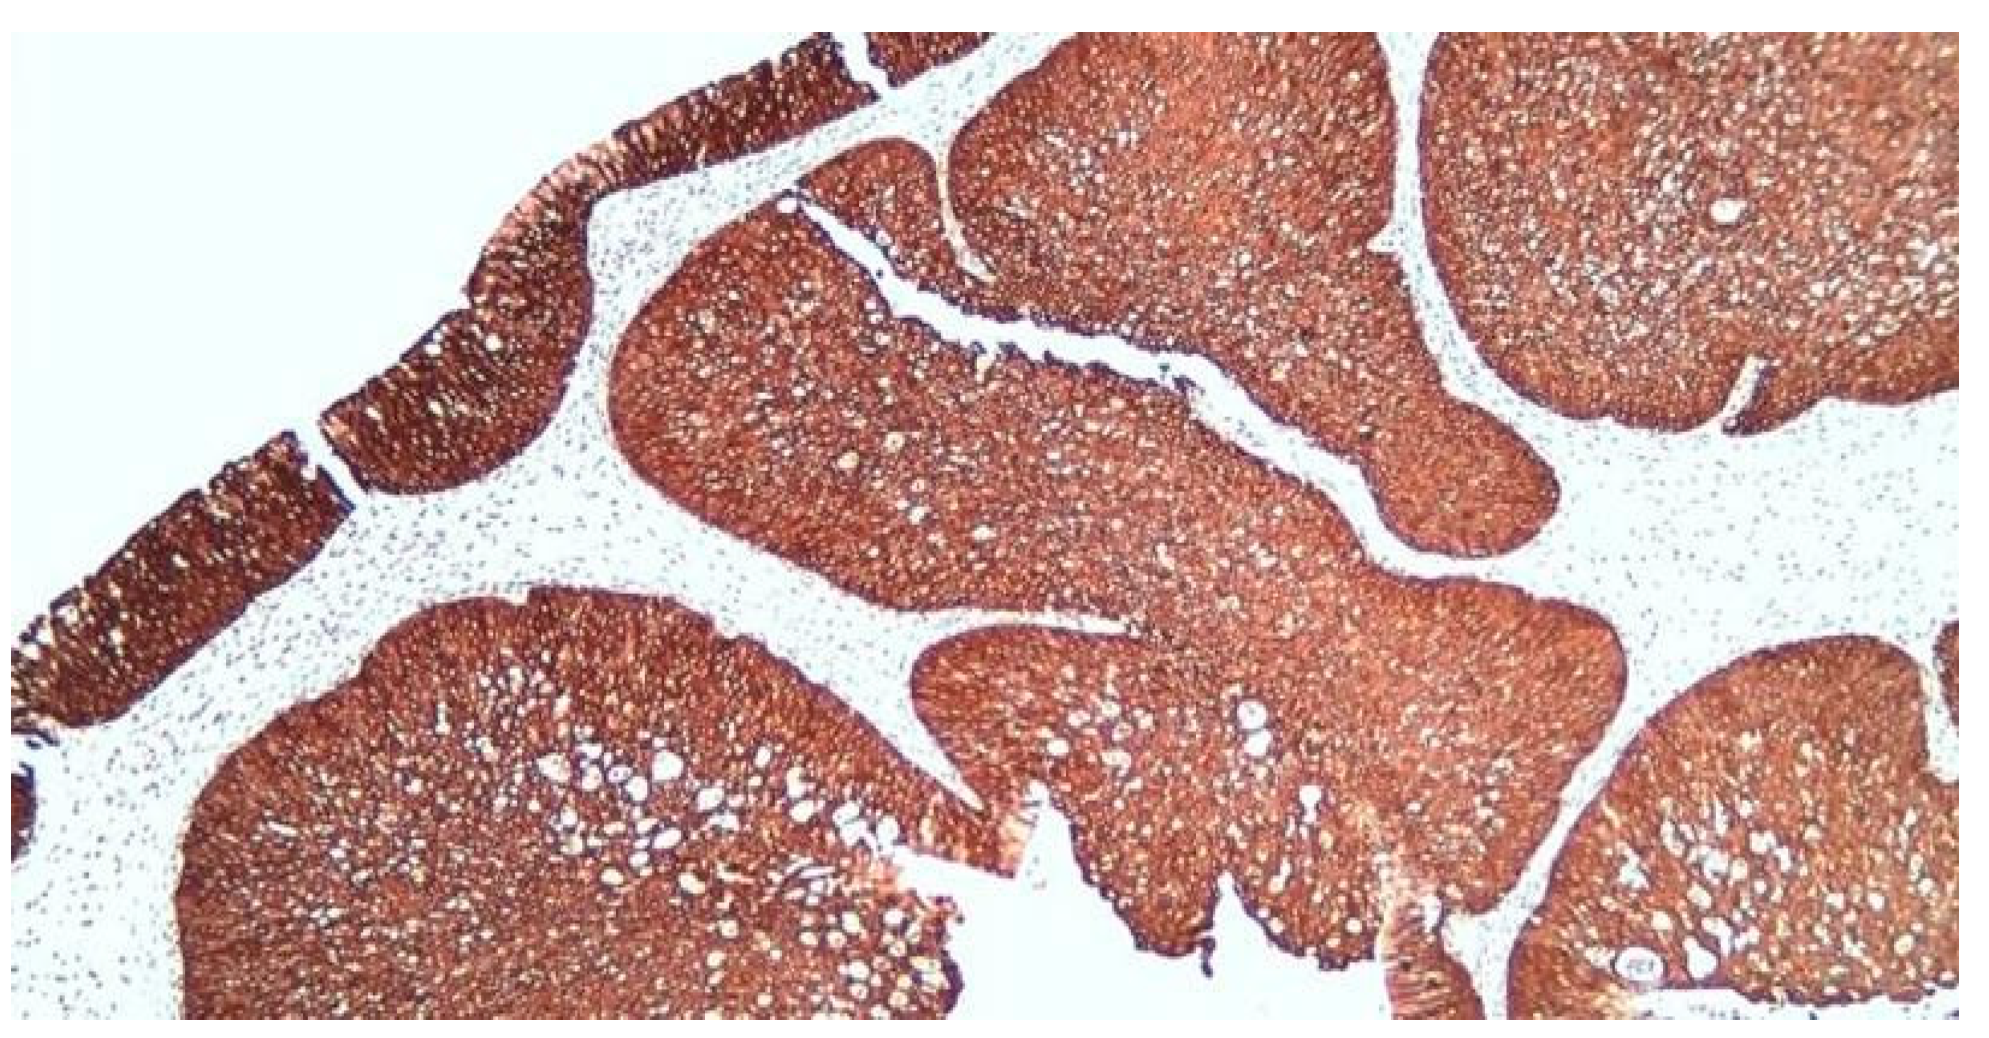

Immunohistochemistry (IHC) was performed with the aim of highlighting the possible etiology of the inverted papilloma and to follow the invasive nature and possible malignant transformation. We opted for immunolabeling for Cytokeratin 5 (CK5), nuclear protein Ki-67, protein p16 and the p53 suppressor gene expression (protein). In our study, IHC results were as presented below. CK5 immunolabeling: CK5 membrane and cytoplasmic markers, positive diffuse throughout the thickness of the epithelium in the squamous areas, predominantly basal and in the intermediate layers in the transitional areas and with respiratory columnar epithelium; the mucus-secreting cells embedded in the metaplastic and surface epithelia were negative (Figure 8).

Figure 8.

Diffuse positive CK5 in squamous and transitional epithelial areas, x100.